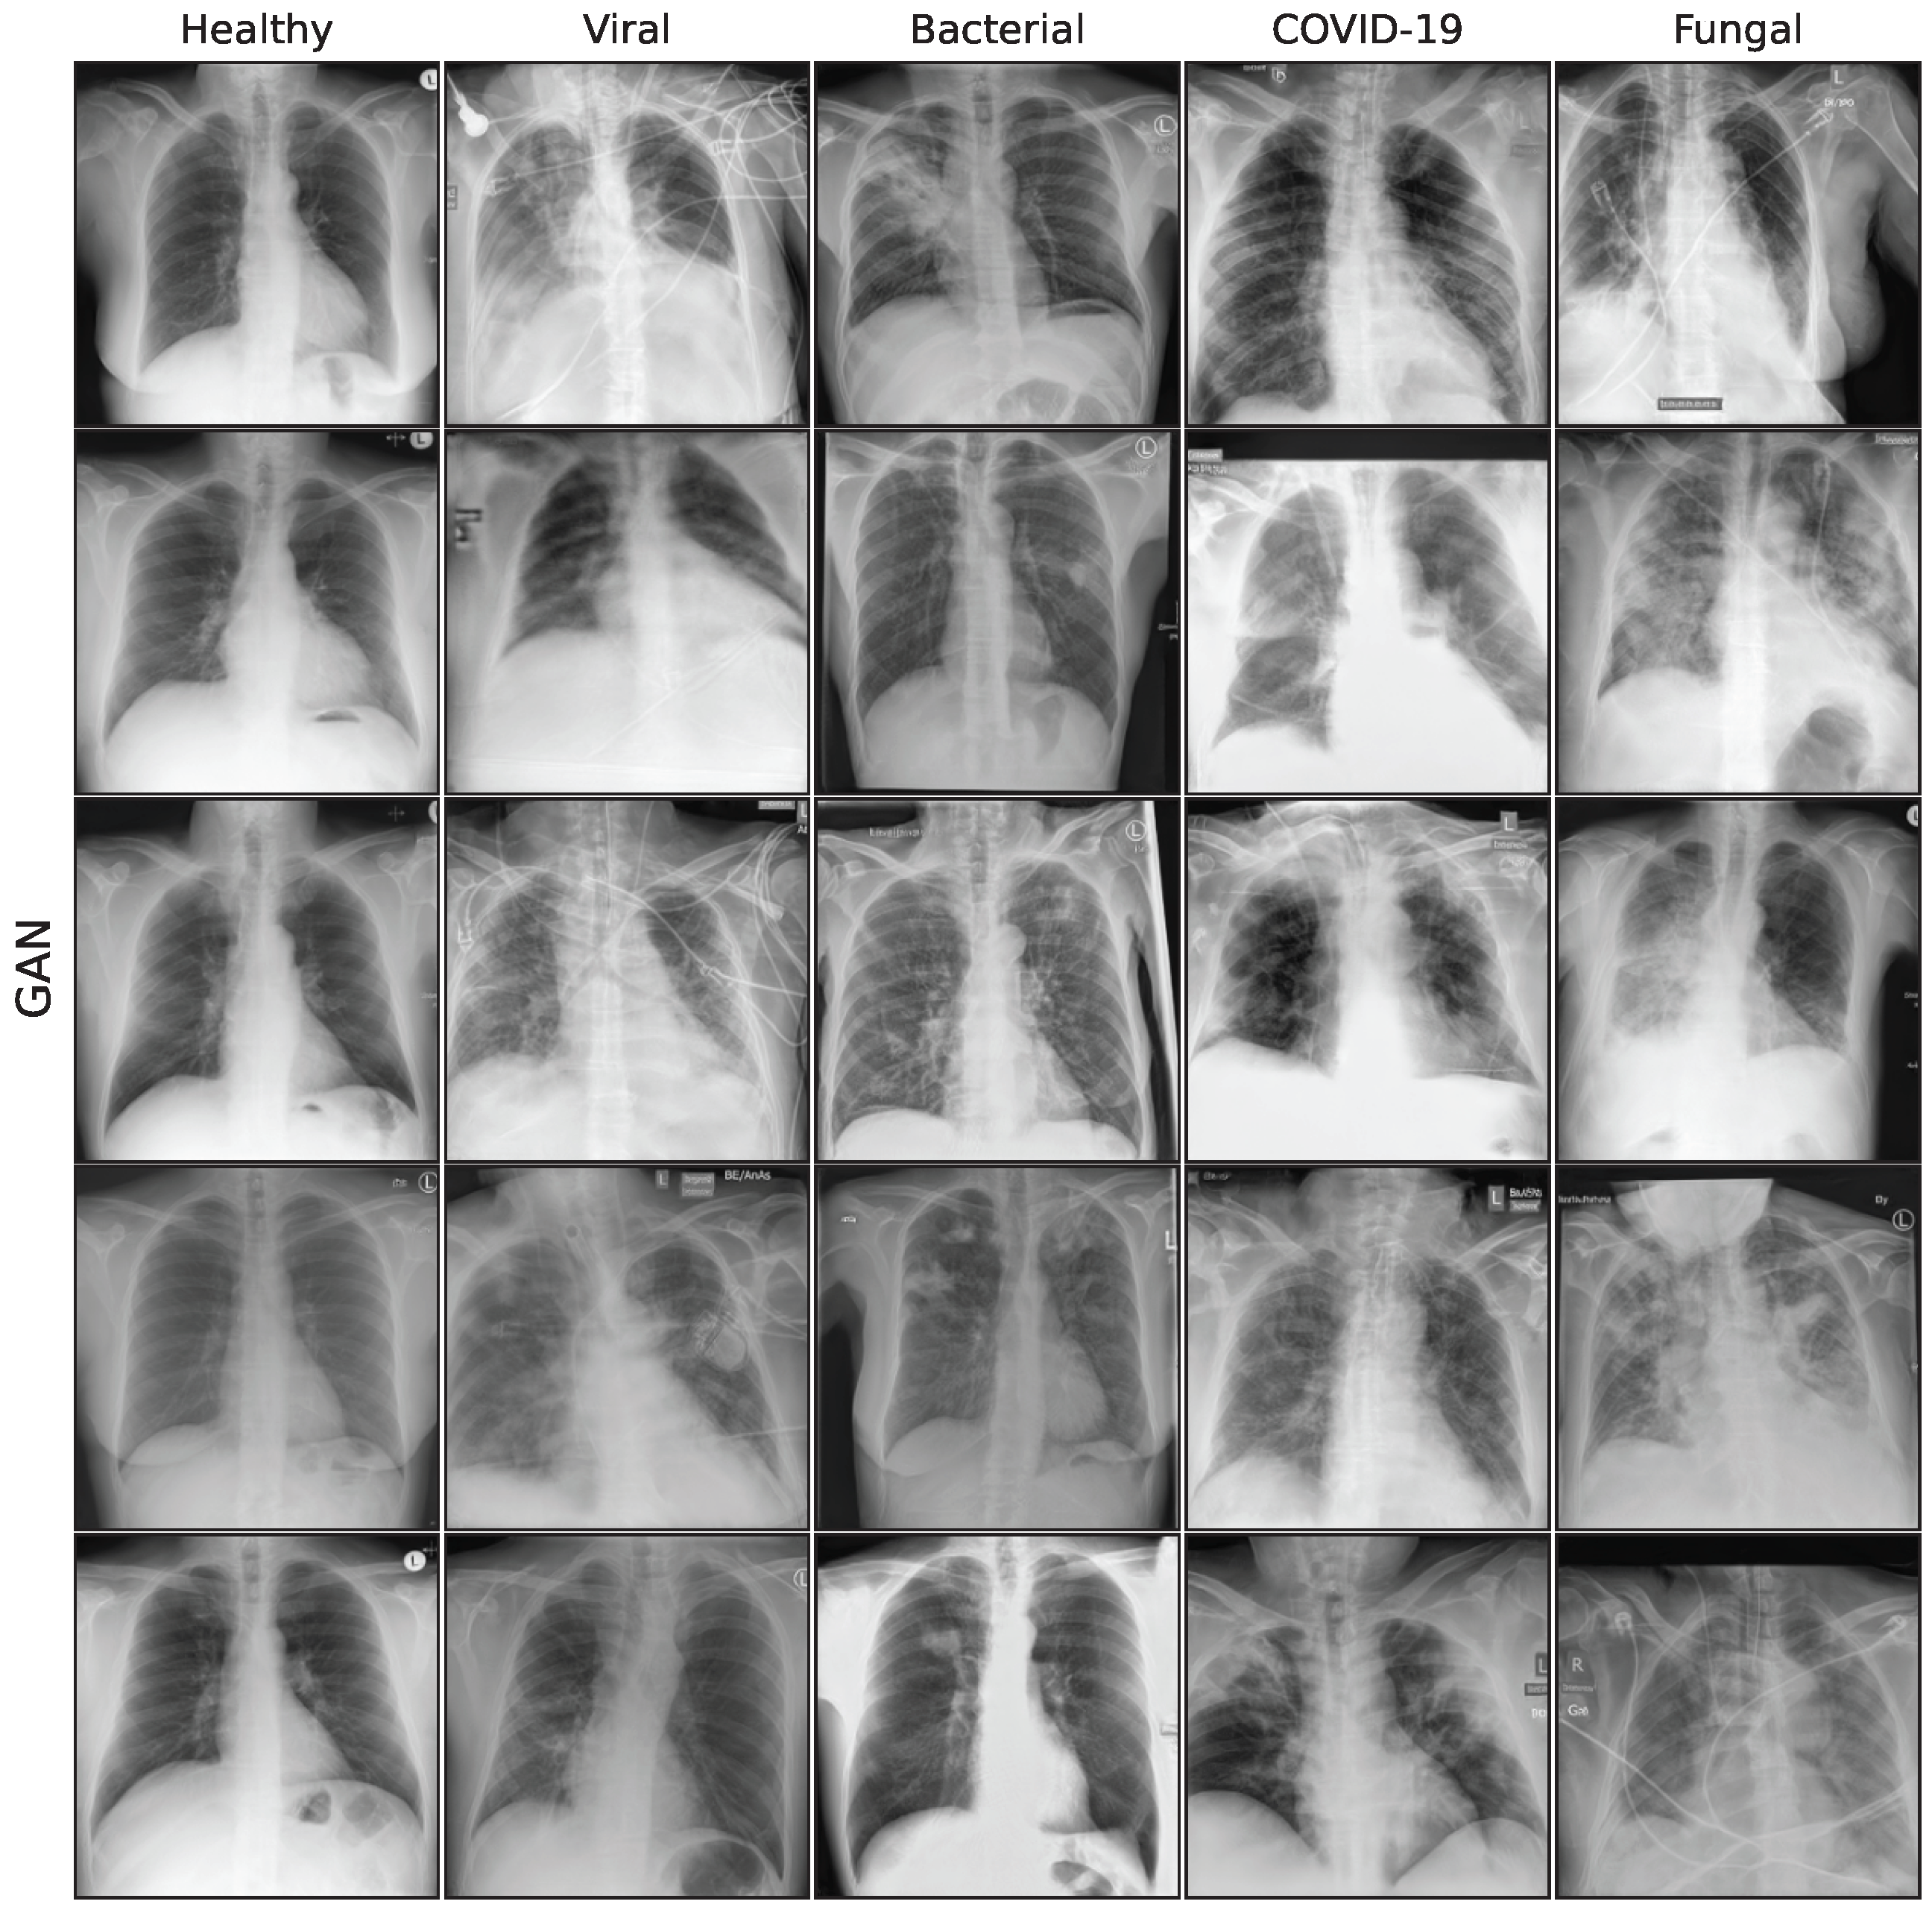

3.2. Image Synthesis

This subsection describes the generative models used in this work. We utilize a special GAN model, a Denoising Diffusion Probabilistic Model (DDPM), and 3 different fine-tuning approaches for a Stable Diffusion [34] model: standard fine-tuning, Low-Rank Adaption (LoRA), and DreamBooth. Our aim is to compare the performance of a GAN model to more recent diffusion-based architectures, building on the GAN proposed in Schaudt et al. [35]. Figure A2 in the Appendix A shows a collection of synthetic images for all generative models.

Figure A2. Sample synthetic images from all classes and methods.

Bioengineering 10 01421 g0a2